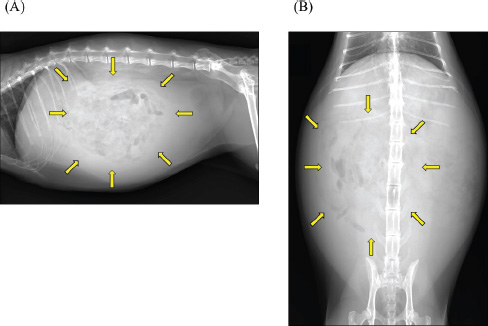

A 2-year-old castrated male domestic shorthair cat, weighing 5.3 kg, presented with a 2-month history of abdominal distension and a 4-day history of anorexia. There was no history of illness or abdominal surgery. Physical examination revealed severe abdominal distension with a fluid wave and mild hypothermia (37.1°C). Blood tests revealed mild elevations in blood glucose (178 mg/dl; reference interval 71–148 mg/dl) and serum amyloid A (5.27 µg/ml; reference interval <3.75 µg/ml) levels, while lipase activity was within normal limits (23.9 U/l; reference interval <30 U/l). Abdominal radiography revealed increased radiopacity and digestive tract consolidation (Fig. 1). Abdominal ultrasonography revealed severe ascites, small intestine hypoperistalsis, pancreatic enlargement, and irregular thickening of the peritoneum with several nodules (Fig. 2). Echocardiography revealed no abnormality. In the ascitic fluid analysis, the total nucleated cell count was 1,000 cells/μl with no evidence of neoplastic cells or bacterial infection, and the specific gravity of the supernatant was 1.024, confirming the ascites as a modified transudate (Fig. 3). Feline infectious peritonitis was considered unlikely due to the absence of feline coronavirus genes in the ascitic fluid and no elevation in blood anti-coronavirus antibody titers. Based on the imaging findings, such as peritoneal thickening, gastrointestinal tract consolidation, and severe ascites, EPS was initially suspected. These findings are consistent with the typical presentation of EPS, characterized by fibrotic thickening of the peritoneum and encasement of abdominal organs (Gremillet et al., 2022). However, the possibility of malignancy was deemed unlikely due to the cat’s relatively young age. A trial treatment with prednisolone (10 mg/head, q24 h) and enrofloxacin (25 mg/head, q24 h) was initiated to manage the suspected inflammatory process and potential bacterial infection, respectively. However, no clinical improvement was observed, suggesting that the underlying condition might be more complex than initially suspected. A non-sedated computed tomography (CT) scan was performed to obtain more detailed diagnostic information on day 12 after presentation. A Siwtenn-slice multi-slice CT scanner (Aquilion™ Lightning, Canon Medical Systems, Japan) was used without anesthesia, with the patient restrained in an acrylic cage (CT capsule, Terucom, Japan). The following technical parameters were used: rotation time=0.75 s; slice thickness=1 mm; reconstruction interval=0.5 mm; table speed=16 mm/rotation; helical pitch=16.0; X-ray tube voltage=120 kV; and X-ray tube current=100 mA. The CT scan revealed a tumor-like enlargement of the pancreas, irregular scattered nodular formations aggregating dorsally in the peritoneum, and ground-glass opacity in the right lower lobe of the lung (Fig. 4). Because angiography was not performed, the vascular characteristics and more detailed differentiation of the soft tissue masses could not be assessed. A pancreatic tumor was suspected; however, diagnostic and therapeutic surgical interventions were deemed difficult due to the animal’s condition. In addition, the owner declined further invasive procedures, such as fine-needle aspiration or laparoscopy. Despite prednisolone treatment (5 mg/head, 24 h), ascitic fluid drainage, and fluid therapy, the cat died 19 days after the first presentation.

Fig. 4. CT scan. Transverse CT images of (A) upper abdomen and (B) chest are shown. The mesenteric fat exhibited scattered nodules with irregular contours (arrow) centered around the enlarged and tumorous pancreas (*). Ground-glass opacity was observed in the right lower lobe of the lung (arrowhead).